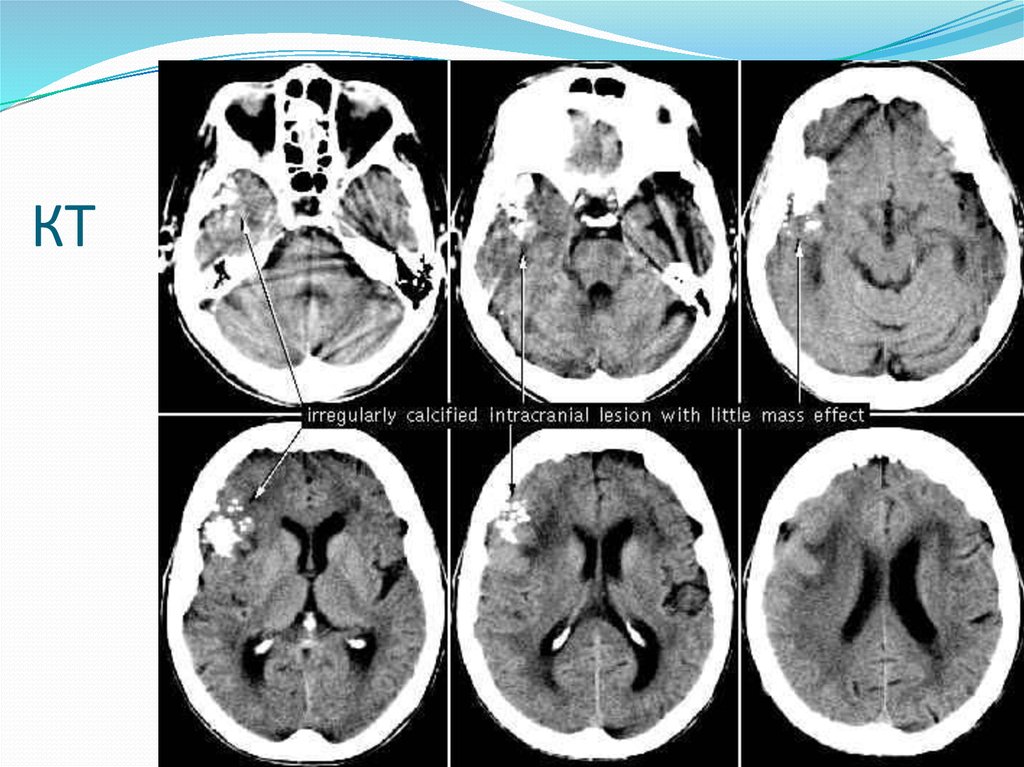

4. Астроцитома

5. кт